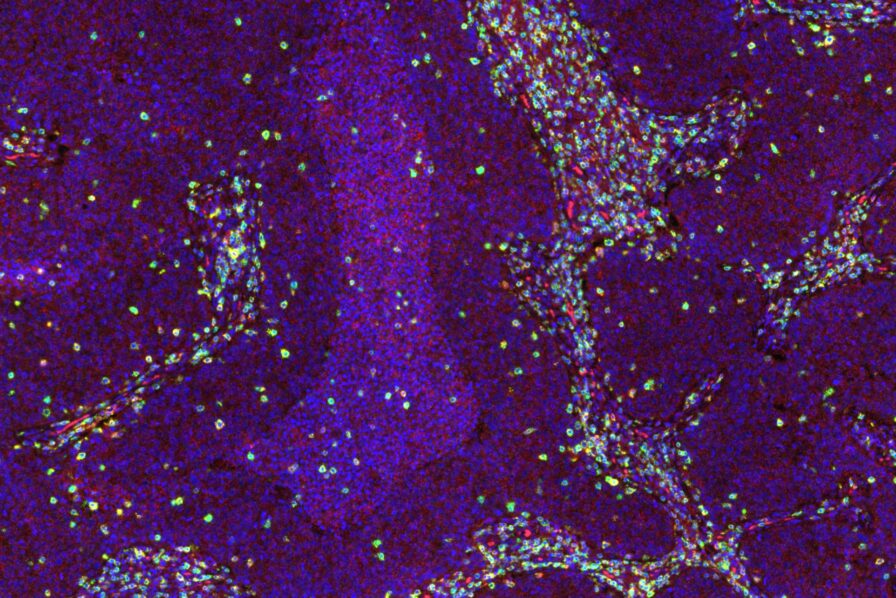

Human Tissue Models

Mattek’s lab-grown human epithelial tissues are living, metabolically active 3D tissue models that provide greater insight into clinical outcomes.

Visikol Products

We offer several reagents and supporting materials that provide researchers with an unprecedented view of tissues for enhanced characterization.